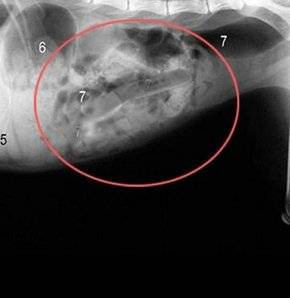

Hollanda'da bir kadın 78 parçalık çatal bıçak takımı yutmuş